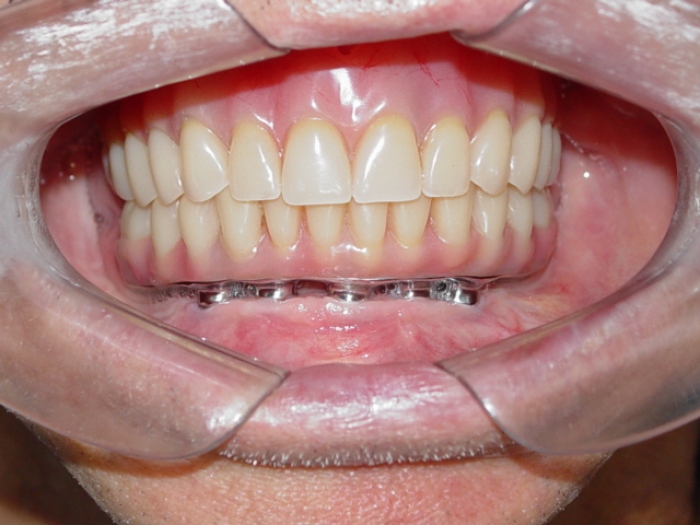

Prótese fixa em resina

Sorriso final